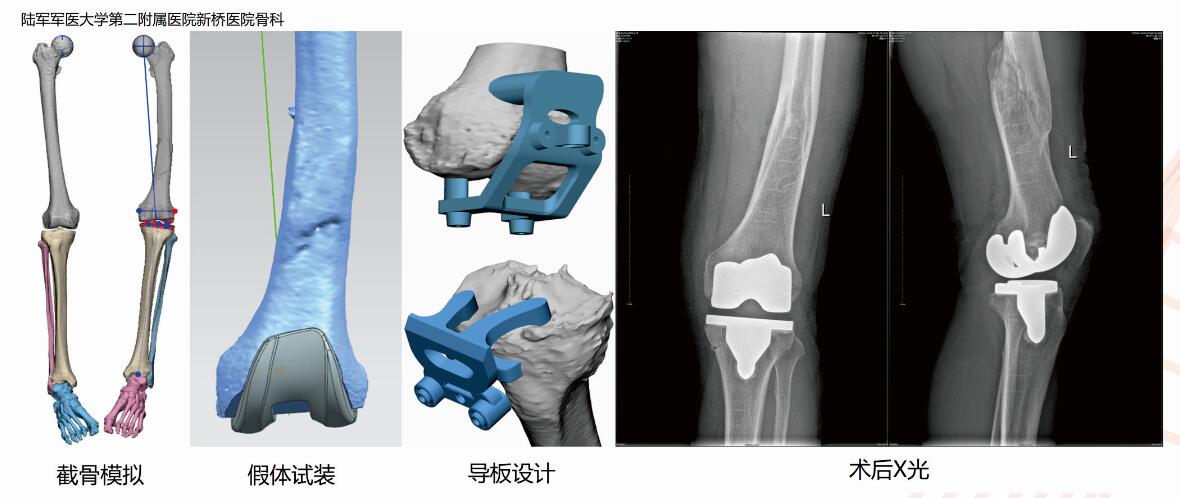

陆军军医大学第二附属医院新桥医院骨科,患者刘先生,64岁,类风湿性关节炎,股骨干陈旧性骨折30年,疼痛4年。因股骨干骨折畸形愈合,髓内杆无法通过或偏差较大,针对类似膝关节患者,医生采用双下肢全长CT扫描,层间距0.625mm,层厚0.625mm,双下肢三维重建,计算机测量外翻角度、旋转角度等,确定截骨位置及模拟假体型号、安装效果,设计截骨定位导板术中辅助截骨及假体安装,以减小术中人为及传统器械设计因素所导致的偏差。